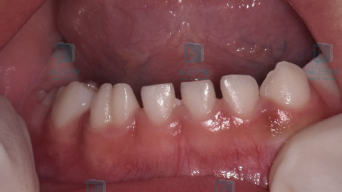

图片

健康的乳牙列有散在生理间隙